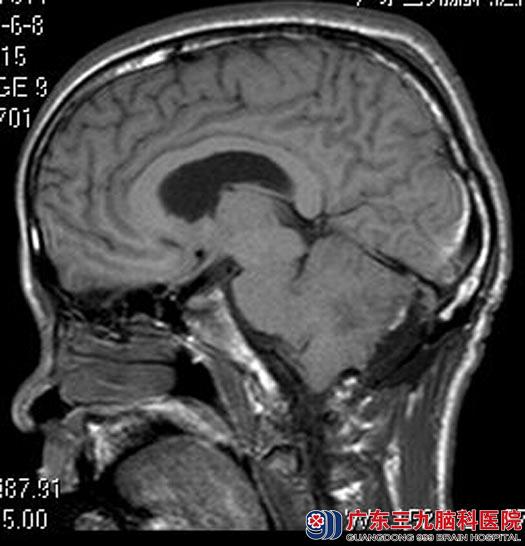

广东三九脑科医院头颅MRI检查结果:右侧小脑半球占位,大小约3.7cm×5.4cm×4.4cm,幕上脑积水,考虑小脑发育不良性神经节细胞瘤可能性大。

手术前